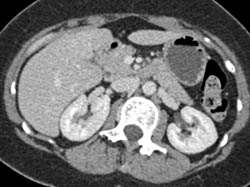

Focal Nodular Hyperplasia (FNH)